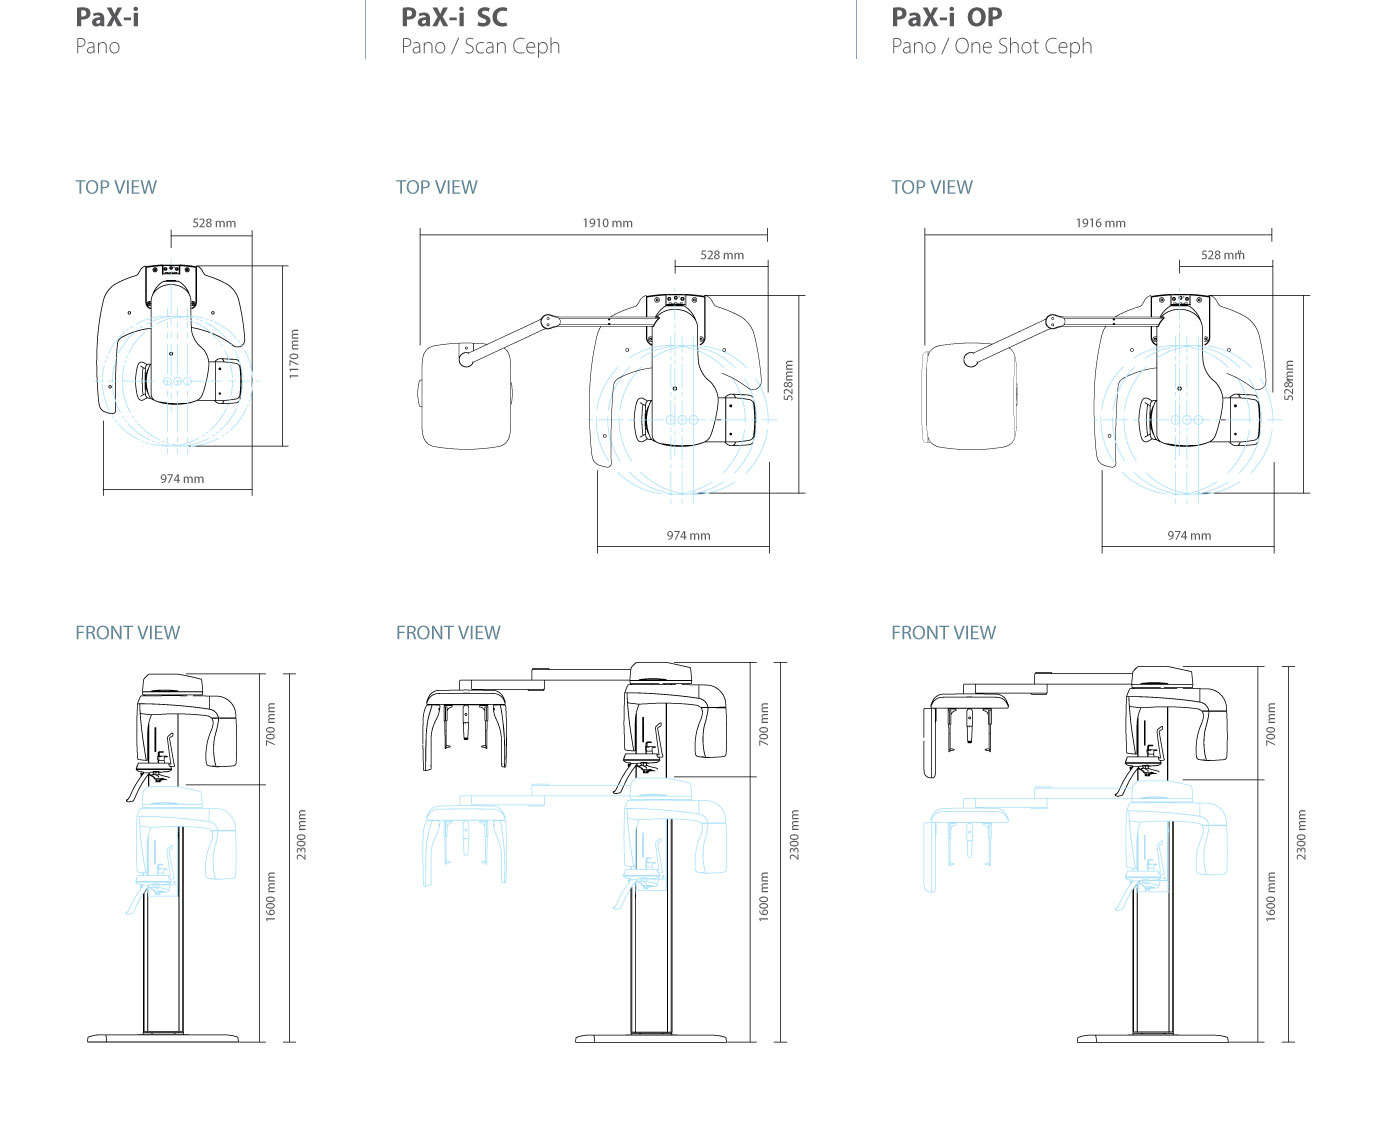

DIMENSIONS [Unit : mm]

PaX-i OPG

PaX-i OPG

DIMENSIONS [Unit : mm]